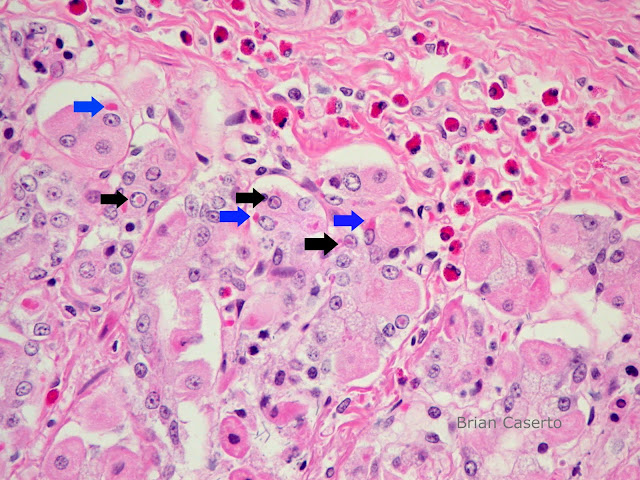

Distemper canine virus stomach inclusions eosinophilic racoons nuclei cytoplasm mucosal epithelium blue black pathology veterinary

Canine Distemper Virus In 2 Racoons | Veterinary Pathology

Canine Distemper Virus in 2 Racoons | veterinary pathology vetpath.wordpress.com

distemper canine astrocyte inclusions racoons veterinary

Canine distemper virus in 2 racoons. Toronto sees increase in raccoons infected with canine distemper virus. Parks department warns of raccoon distemper in prospect park